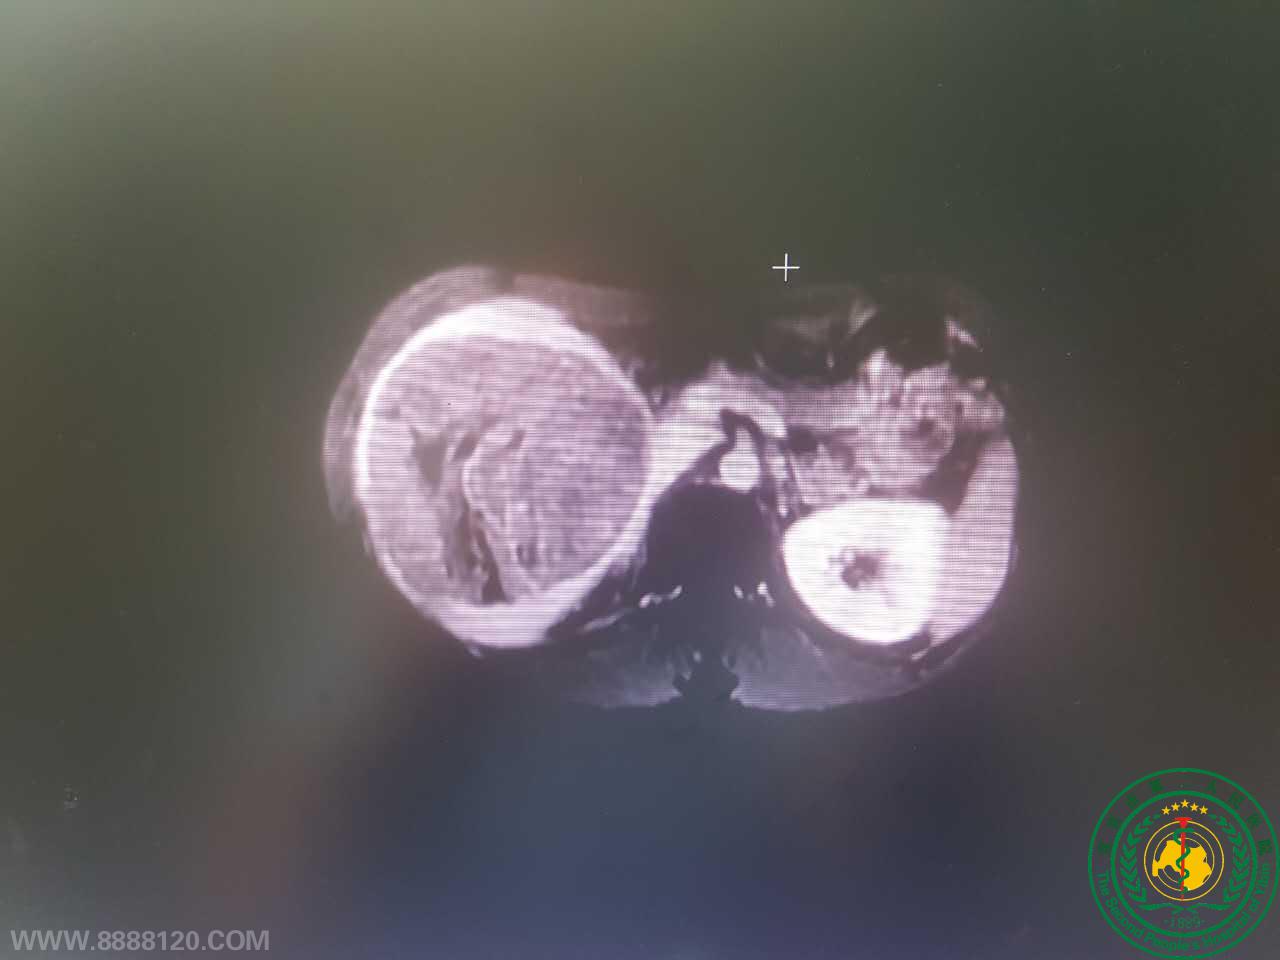

宜宾市二医院肝胆胰外科顺利完成了宜宾市第一例完全腹腔镜下前入路标准右半肝切除术

宜宾市二医院肝胆胰外科顺利完成了宜宾市第一例完全腹腔镜下前入路标准右半肝切除术13813